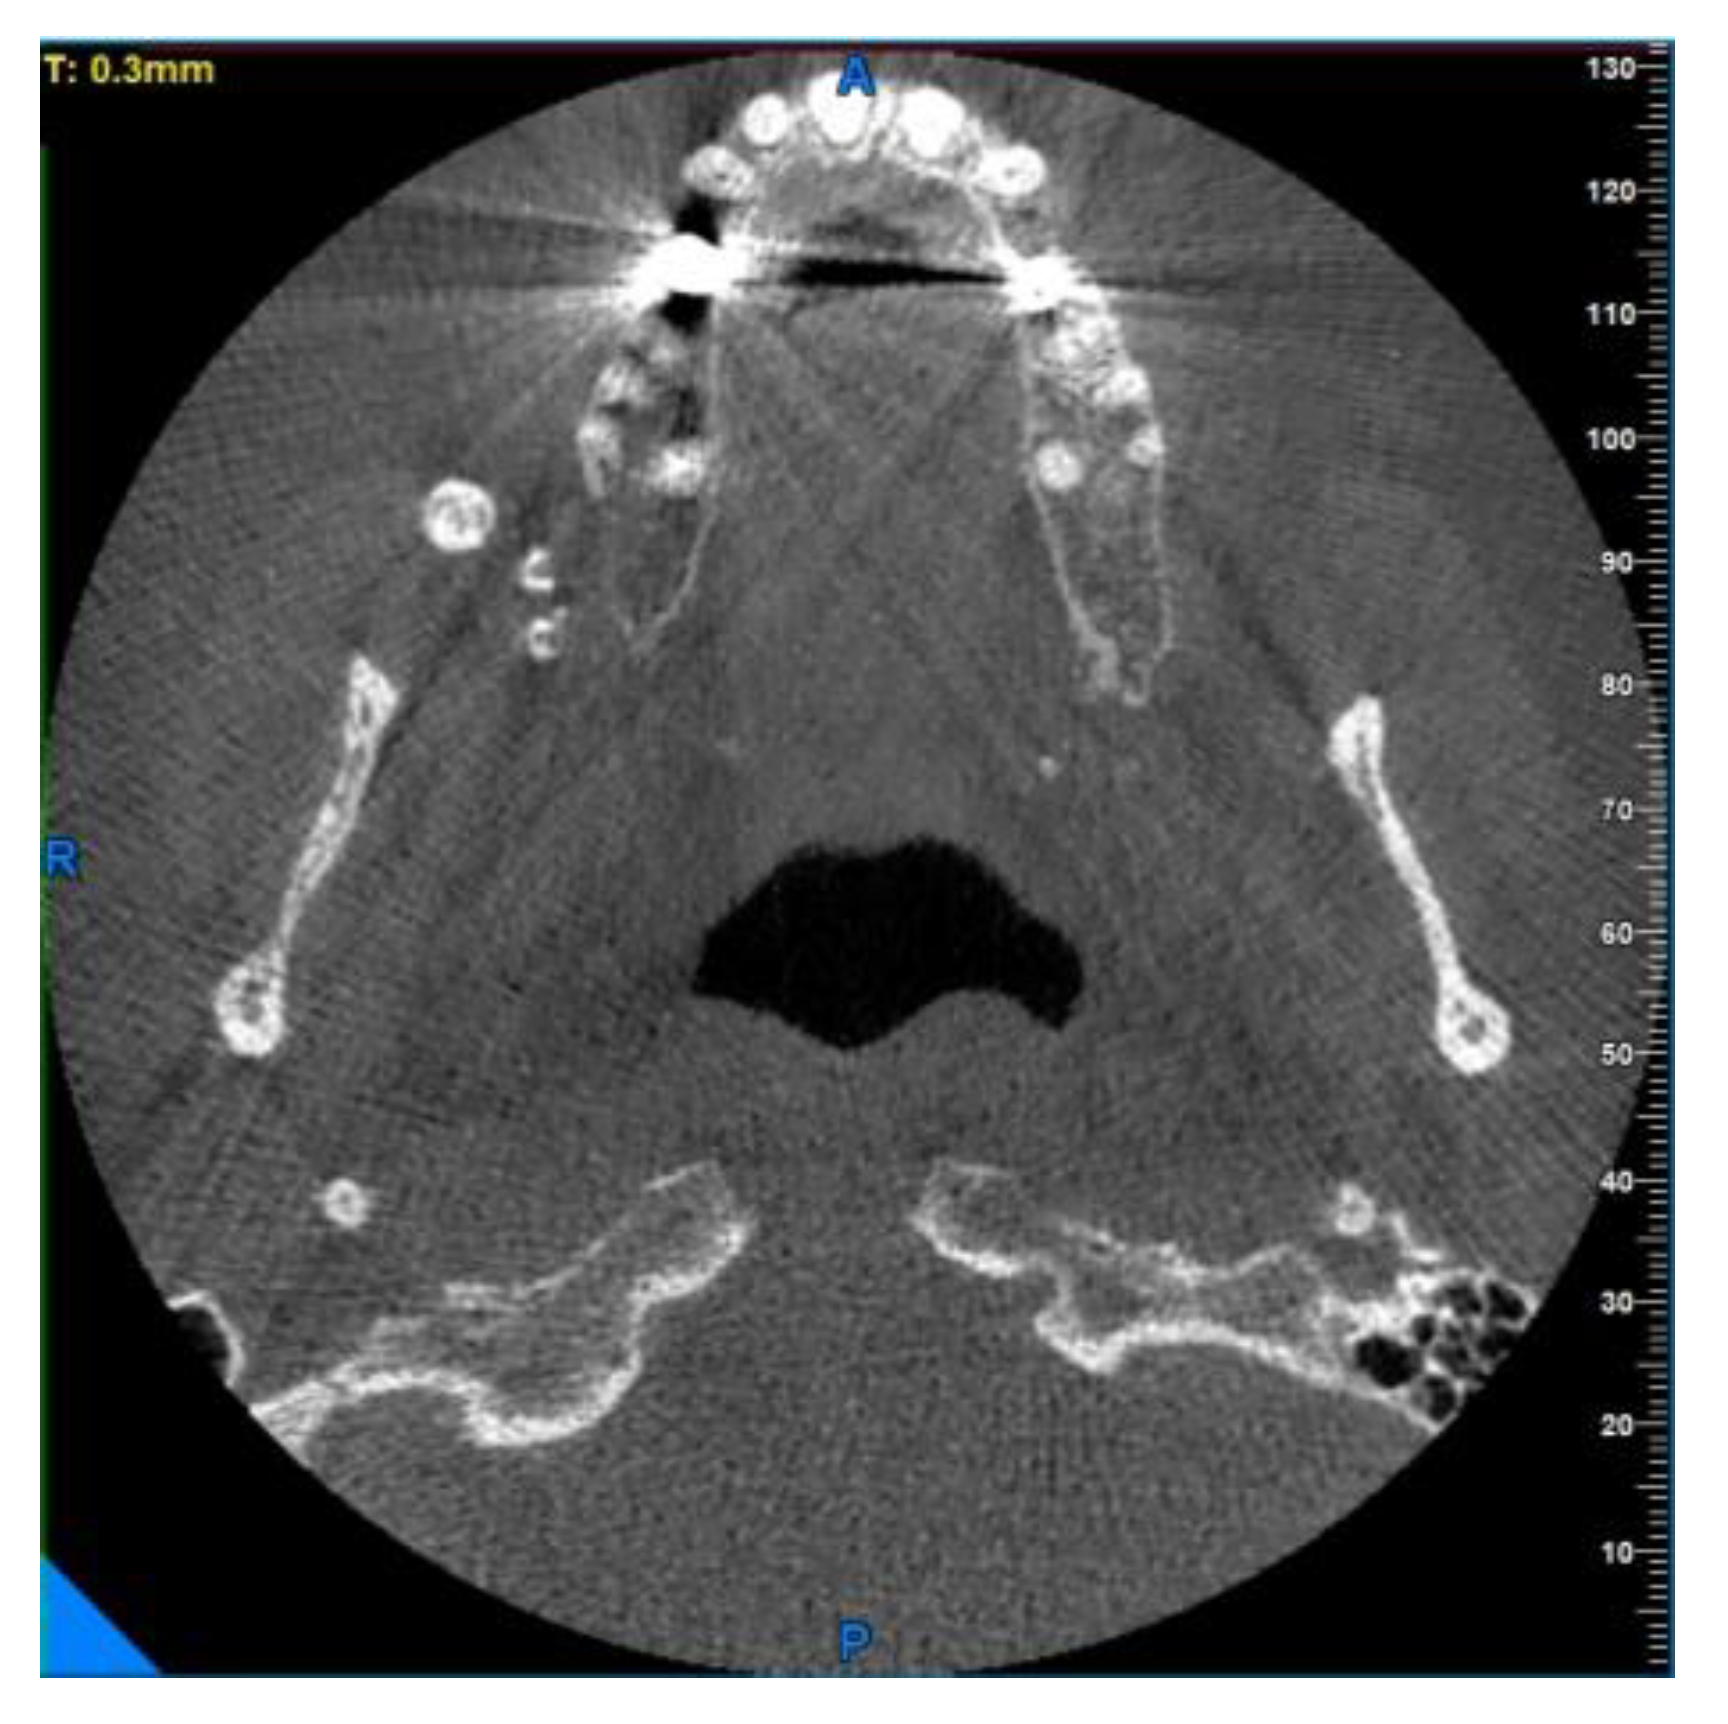

2. Case Presentation